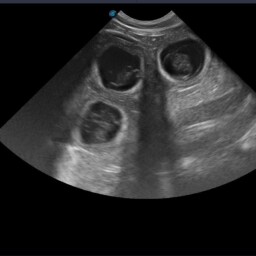

• Monitorowanie przebiegu ciąży (USG bardzo wysokiej jakości, RTG, badania hormonalne)

• Biometria płodowa (wyznaczanie terminu porodu na podstawie pomiarów struktur płodowych)